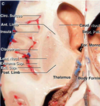

Key gyri on the lateral surface of the frontal lobe

Superior frontal gyrus

Middle frontal gyrus

Inferior frontal gyrus (pars triangularis, pars orbitalis, pars opercularis)

Precentral gyrus

Key sulci on lateral surface of frontal lobe

Superior frontal sulcus

Inferior frontal sulcus

Pre-central sulcus